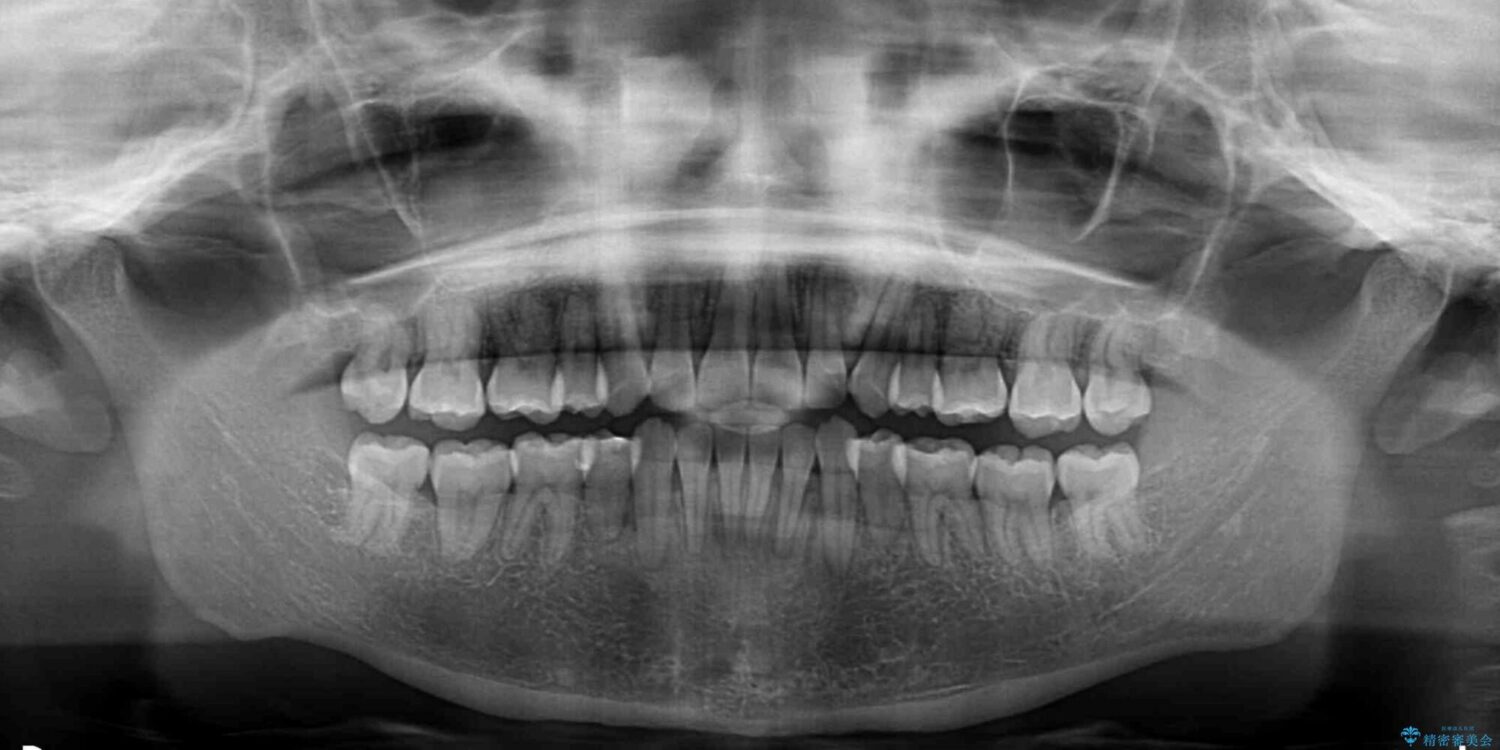

下唇が突き出るような口元の突出感が気になるとのことで来院された患者様です。

上下顎ともに前突した歯列であったので、上下ともに左右の第1小臼歯4本を抜歯し、ワイヤー装置にて矯正治療を行うこととしました。

治療前